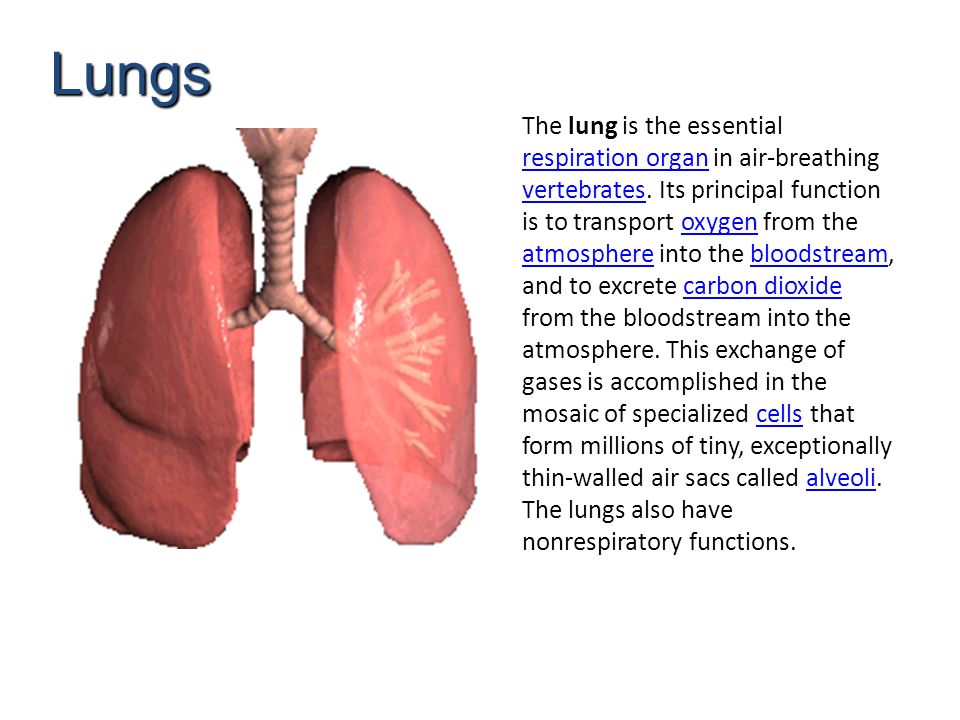

(1 ) nostrils (2) larynx (3) pharynx (4) trachea (wind pipe) (5) bronchi (6) lungs (7 ) bronchioles (8) alveoli (9) mouth

(5) Lungs: each bronchus leads into a lung. Inside the lungs are tiny tubes called bronchioles. The bronchioles branch again into alveoli.

(1 ) nostrils (2) larynx (3) pharynx (4) trachea (wind pipe) (5) bronchi (6) lungs (7 ) bronchioles (8) alveoli (9) mouth

(5) Lungs: each bronchus leads into a lung. Inside the lungs are tiny tubes called bronchioles. The bronchioles branch again into alveoli.